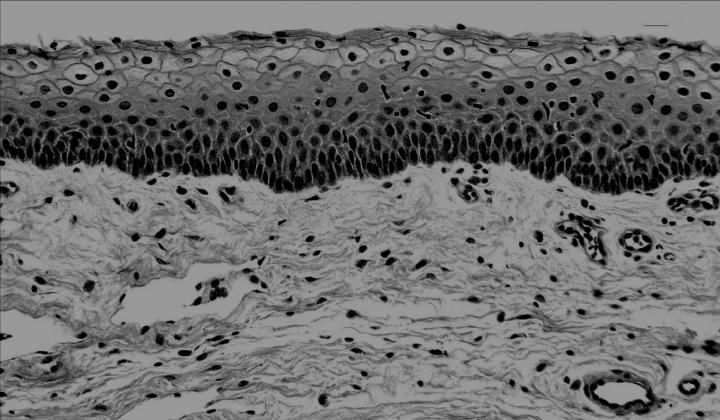

"Many of the infections caused by these two bacteria start on the skin or on the mucosal surfaces that line body cavities like the nose, mouth and throat, the gut, and the vagina. The ability of these bacteria to cause disease depends on production of a family of toxins known as superantigens, which cause exceptionally harmful inflammation," explains Patrick Schlievert, PhD , professor and head of microbiology and immunology at the University of Iowa Carver College of Medicine and lead author of the new study.

Previous work by Schlievert showed that superantigens cause the epithelial cells of the mucosal barrier to make signaling molecules called chemokines. Those chemokines attract immune cells that disrupt the integrity of the mucosal barrier, allowing the superantigens and frequently the bacteria themselves to penetrate and cause serious and often fatal diseases, including toxic shock syndrome.

In the new study, Schlievert and his colleagues at the UI and National Jewish Health in Denver used human vaginal epithelial cells as a model of a mucosal barrier. They showed that the interaction between CD40 and superantigens triggers the production of chemokines in these cells. Removing CD40 from the cells using CRISPR gene editing prevented bacterial superantigens from triggering the production of the chemokines. In contrast, restoring CD40 to those cells restored the ability of superantigens to trigger chemokine production.